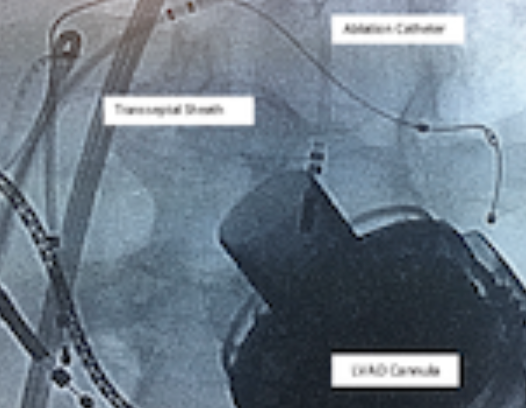

The patient was brought to the electrophysiology lab in a stable paced rhythm (atrial, biventricular). The procedure was performed on uninterrupted warfarin (INR of 2.1). His BiV-ICD was interrogated prior to the procedure; tachy therapies were programmed off, leaving detection on, and the device was set to pace (DDD) at 70 beats per minute during mapping. The mode was changed to DOO during ablation with arrhythmia detection off. A transseptal approach was used for left heart access using a large curl deflectable sheath (Agilis, Abbott) and BRK-1 needle (Abbott). A target ACT >350 was maintained. Intracardiac echocardiography (ICE) was used for assisting transseptal puncture as well as for defining anatomical landmarks and monitoring for complications during the procedure. A 4 French quadripolar catheter was placed in the RV apex for pacing and induction. The EnSite Precision Cardiac Mapping System (Abbott) was used for electroanatomic mapping. A high density (>3000 usable points) LV endocardial voltage map was created using the AutoMap feature of the EnSite Precision Cardiac Mapping System and standard cut-off values (dense scar if bipolar voltage <0.5 mV and normal voltage being >1.5 mV). The voltage map showed extensive anterior wall scar from base to apex, most of it very dense with extension to the lateral wall, and multiple areas of patchy scar in the posterolateral LV (from the base to the LVAD cannula suture line). Special care was taken not to enter the VAD cannula with the catheter while mapping. Large areas of late potentials as well as fractionated electrograms were seen in the posterolateral LV, especially towards the apex and around the cannula, as well as in the mid and apical anterior wall. All the fragmented and late potentials were tagged using 3D location markers. (Figures 1A and 1B)

VT was induced with programmed electrical stimulation (triple extrastimuli 600/350/350/350) from the RV. We used a 7 Fr, 20-pole duo-decapolar catheter with 2x2 spacing for activation mapping of VT as well as mapping of late potentials during sinus rhythm. The first induced VT had a right bundle branch block / superior axis morphology with no precordial transition and positive complexes in aVR and aVL; VT cycle length (CL) was 405 milliseconds (ms), and this was hemodynamically well tolerated (VT-1; Figures 4 and 5). With the HeartMate 3 in place, we noted significant surface ECG noise when compared to the HeartMate II devices; interestingly, the noise abated during the “pulse” delivered by the device every 2 seconds. However, no evidence of noise was seen in the intracardiac electrograms (Figure 5). The activation map showed clear evidence for continuous diastolic activity at the low posterolateral LV adjacent to the VAD cannula, and the propagation map also confirmed reentrant nature (Figure 4). The duo-decapolar catheter was replaced with an irrigated ablation catheter (8 Fr FlexAbility, F-J curve, Abbott); mid-diastolic activation during VT was seen, and ablation at this location terminated VT-1 within a few seconds (Figures 2A and 6). Further ablation was done targeting the substrate, and guided by fractionated electrograms and late potentials. Re-induction following this resulted in induction of a second VT with a left bundle branch block pattern with a CL of 440 ms, inferior axis, and V3 transition (VT-2). Activation map performed during VT-2 showed likely a microreentrant circuit within a small area of scar in the mid anteroseptal/anterior wall, where again, continuous diastolic activation was seen. Ablation at this location terminated VT-2 within seconds (Figures 2B and 7). No further sustained VTs were inducible with aggressive extrastimulus testing from the RV and LV. There were no procedure-related complications.

- Fluoroscopic barriers: LVAD cannula and drive line, prior implanted leads, pacing catheters, and transseptal sheath;